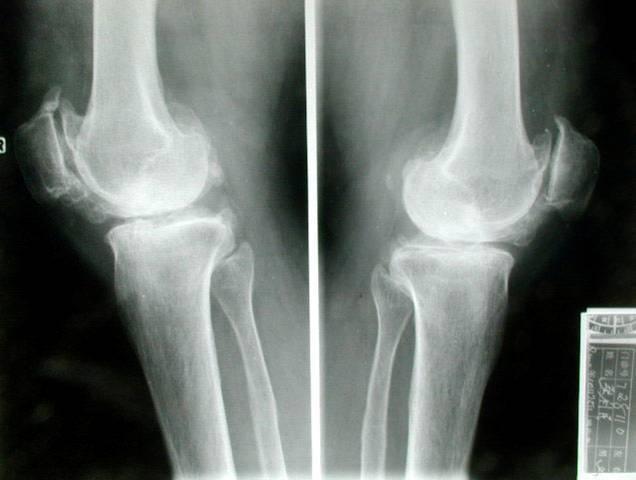

骨质增生图片x光片

膝关节骨质增生图片